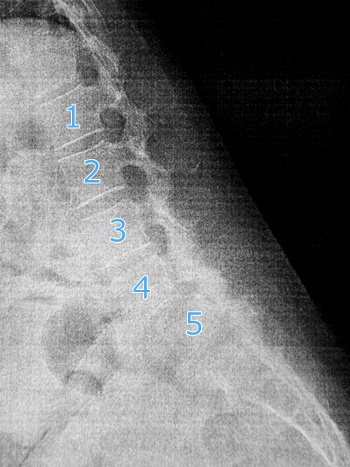

ちなみに紙にプリントしてもらったレントゲン写真、ちょっと見にくいけど横から背骨を見たところ。脊椎の4番が前にすべってるそうです。たしかにすべってるかも。

なんか知らんけど痛そう。そして前かがみのレントゲンがもっと痛そう。

すべってるすべってる(笑) 先生いわく